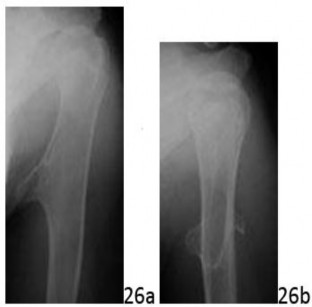

Question 26 A 13-year-old girl injured her left shoulder playing volleyball. The shoulder was previously asymptomatic. She was referred for evaluation of a left humeral lesion noted on radiographs obtained after the injury. Currently she has returned to playing volleyball and is asymptomatic again. AP and lateral radiographs of the shoulder are seen in Figures 26a and 26b. What is the next most appropriate step in management of this patient?

Question 26 A 13-year-old girl injured her left shoulder playing volleyball. The shoulder was previously asymptomatic. She was referred for evaluation of a left humeral lesion noted on radiographs obtained after the injury. Currently she has returned to playing volleyball and is asymptomatic again. AP and lateral radiographs of the shoulder are seen in Figures 26a and 26b. What is the next most appropriate step in management of this patient?

1. ## MRI

2. ## CT

3. ## Bone scan

4. ## Needle biopsy

5. ## Observation

DISCUSSION: The radiographs reveal an osteochondroma of the left humerus; therefore, no further work-up is needed. The lesion was found as an incidental finding after an injury and since it is asymptomatic, no further treatment is needed except for observation. An MRI scan or a CT scan could be obtained to evaluate the thickness of the cartilaginous cap if a secondary chondrosarcoma is suspected in an enlarging lesion in an adult. These studies could also be obtained to define anatomic relationships if surgery is planned. A bone scan could be used to identify other lesions but would not likely provide useful information for this patient. Needle biopsy would not provide any useful information. The Preferred Response # 26 is 5.